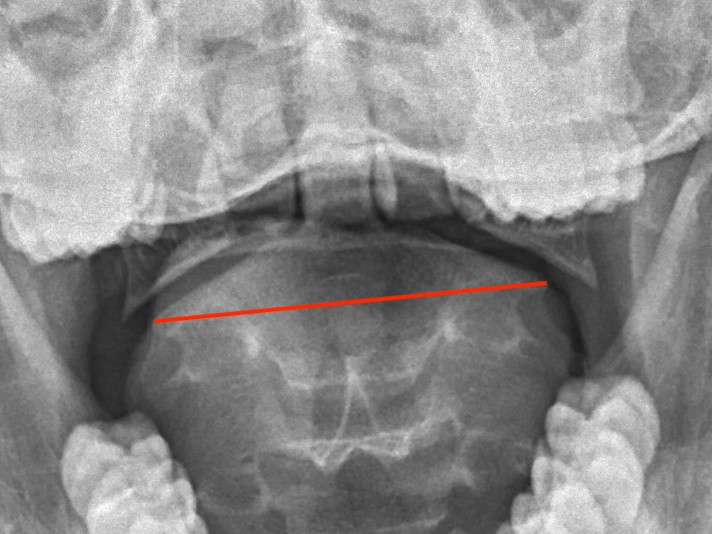

LMD

Lateral mass displacement

LMD 1LMD 2

Increased lateral mass displacement of 8 mm